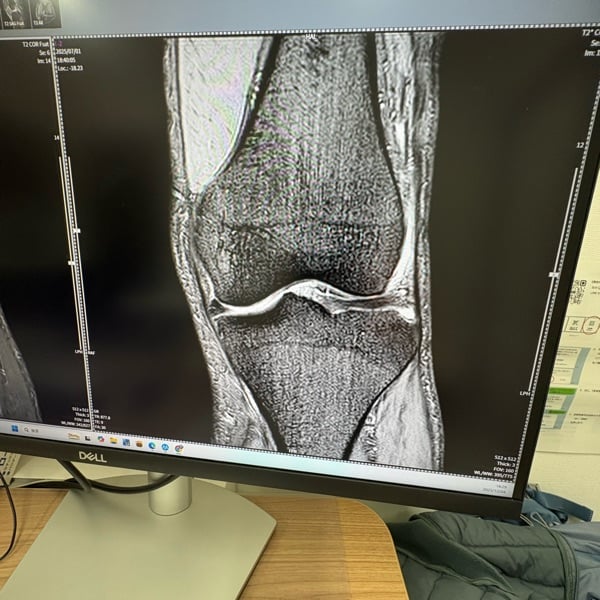

544 AI画像診断!の話し

おはようございます😃 初霜の三重県津市です! 今日のラジオ📻は昨夜整形外科受診した時の待ち時間に画面に出ていた膝の画像をチャッピーさんに見せみた結果についてです。 #AI #画像生成 #画像診断 #毎日配信 #スタエフ毎日配信

MRIの画像をAIに見せるのなんて思いもしなかった 多少は参考になりますね